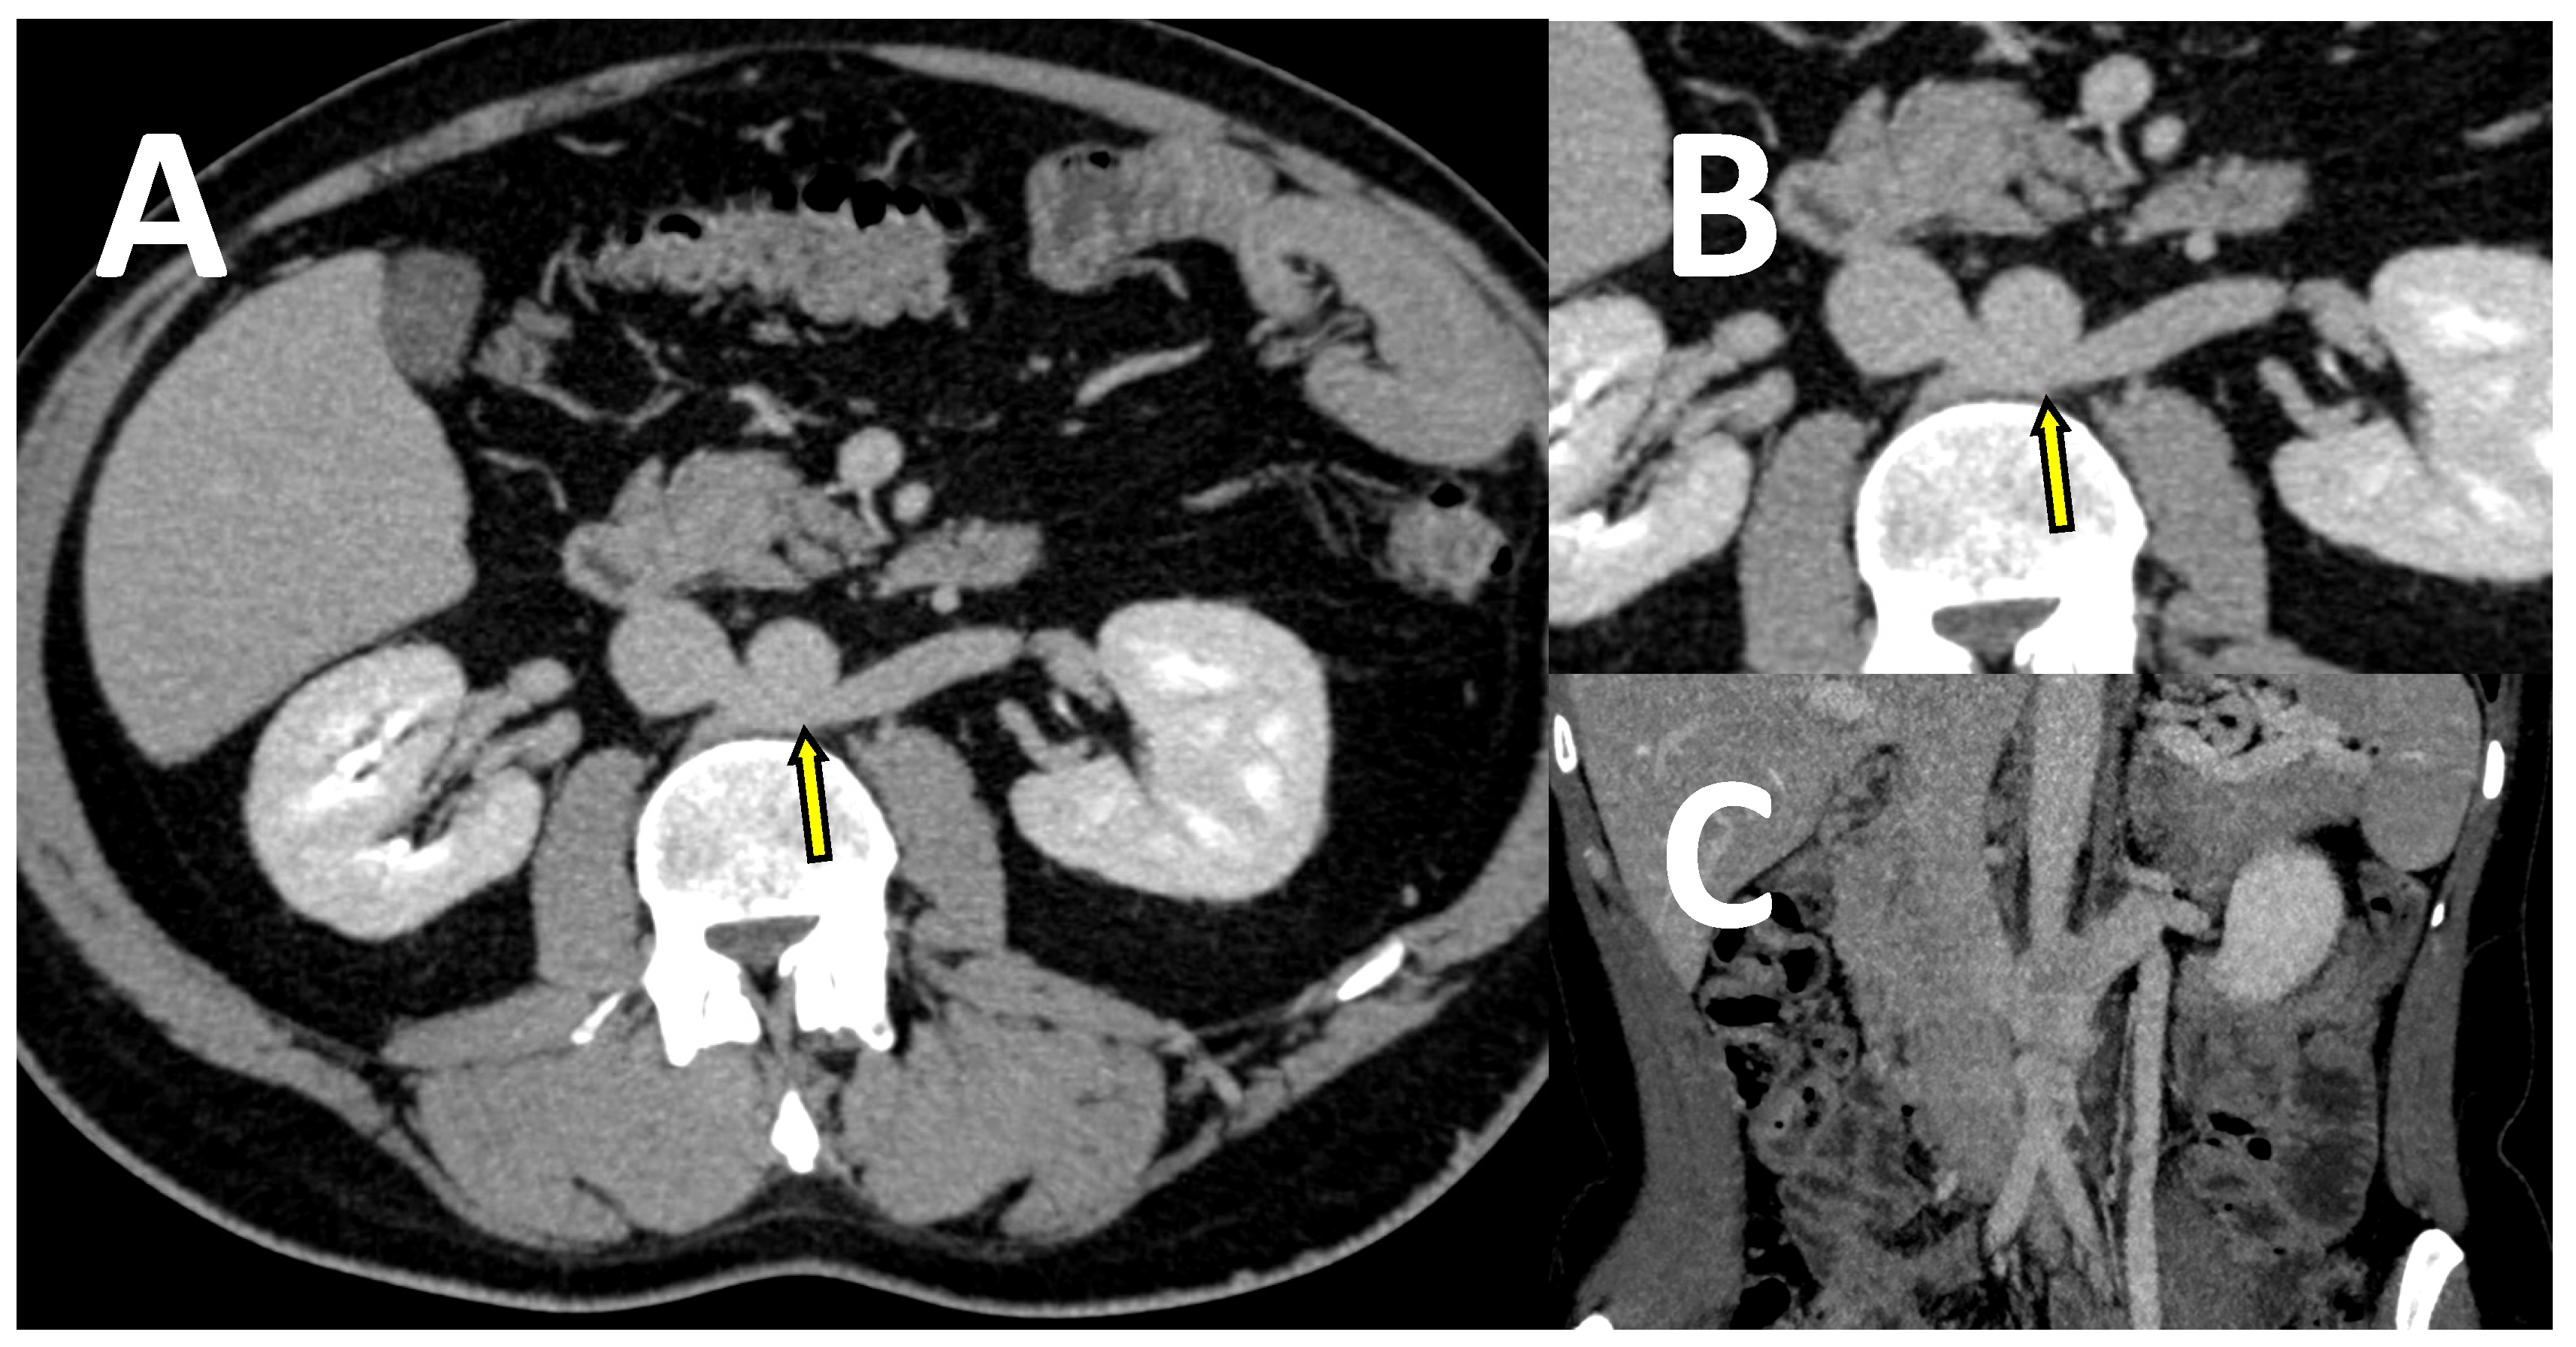

- Coakley, F.V.; Varghese, S.L.; Hricak, H. CT and MRI of pelvic varices in women. J. Comput. Assist. Tomogr. 1999, 23, 429–434. [Google Scholar] [CrossRef] [PubMed]

- Park, S.J.; Lim, J.W.; Ko, Y.T.; Lee, D.H.; Yoon, Y.; Oh, J.H.; Lee, H.K.; Huh, C.Y. Diagnosis of pelvic congestion syndrome using transabdominal and transvaginal sonography. AJR Am. J. Roentgenol. 2004, 182, 683–688. [Google Scholar] [CrossRef]

- Ganeshan, A.; Upponi, S.; Hon, L.Q.; Uthappa, M.C.; Warakaulle, D.R.; Uberoi, R. Chronic pelvic pain due to pelvic congestion syndrome: The role of diagnostic and interventional radiology. Cardiovasc. Intervent. Radiol. 2007, 30, 1105–1111. [Google Scholar] [CrossRef]

- Bookwalter, C.A.; VanBuren, W.M.; Neisen, M.J.; Bjarnason, H. Imaging appearance and nonsurgical management of pelvic venous congestion syndrome. Radiographics 2019, 39, 596–608. [Google Scholar] [CrossRef]

- Szary, C.; Wilczko, J.; Zawadzki, M.; Grzela, T. Hemodynamic and radiological classification of ovarian veins system insufficiency. J. Clin. Med. 2021. under review. [Google Scholar]